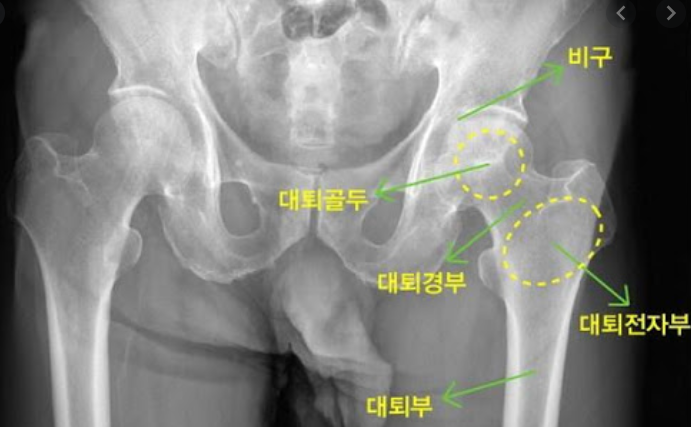

고관절은 골반과 대퇴골을 이어주는 관절입니다. 그래서 엉덩이관절, 엉덩관절 등 여러명칭으로 불리고 있습니다. 고관절이 불편하거나 통증이 있다면 하체를 움직이기에 불편함이 커집니다.

대퇴골두 무혈성괴사

쉽게 말해서 고관절 근처의 혈액순환에 문제가 생겨서 대퇴골 머리 부분에 혈액이 제대로 공급되지않게 됩니다. 이럴 경우 혈액이 공급되지 않아 뼈가 썩게 됩니다.